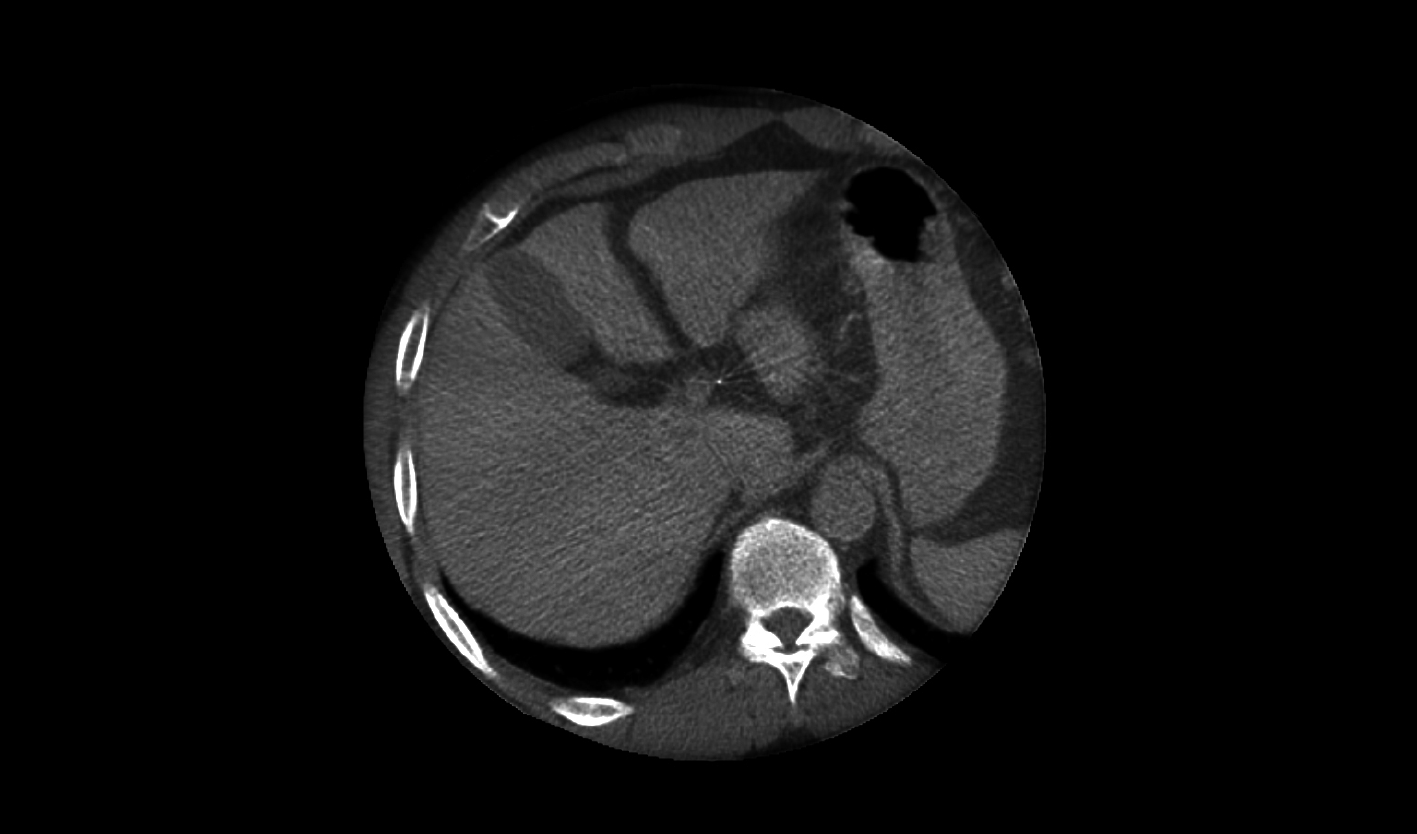

辽阔视野

*40×30cm成像面积,大部位成像一次性覆盖

120cm 大进深覆盖

机架正位满足胸腹部以上介入需求

*230cm 纵向覆盖范围

满足全身介入手术需求,97cm地轨床,快速CPR位